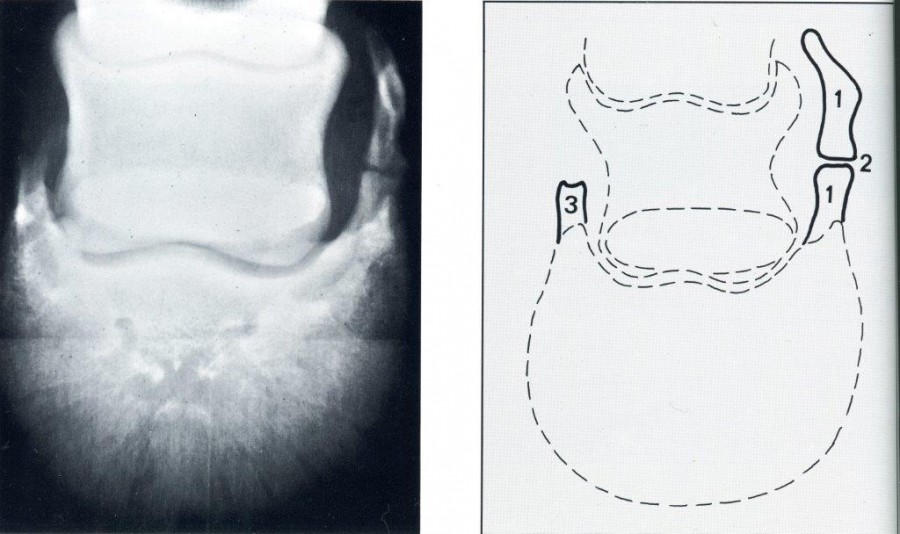

extrait de l'Atlas of diagnostic radiology of the horse. K.J.Dik et L.Gunsser

1) forte ossification du fibro-cartilage latéral. L'ossification débute aussi bien à la pointe qu'à la base du fibro-cartilage. Les deux zones d'ossification ne sont pas entièrement soudées.

2)La ligne éclaircie qui sépare les 2 foyers d'ossification ne doit pas être confondue avec une ligne de fracture.

dixit le Pr Kees J.Dik.